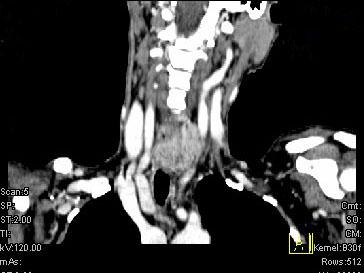

问题 女,50岁,左下颈部扪及一质硬、表面高低不平的包块,肿块逐渐增大,现感吞咽困难,CT如图所示,最可能诊断为 ( )

选项 A、甲状腺原发淋巴瘤 B、颈部神经鞘瘤 C、食管癌 D、喉癌 E、甲状腺癌

答案 E